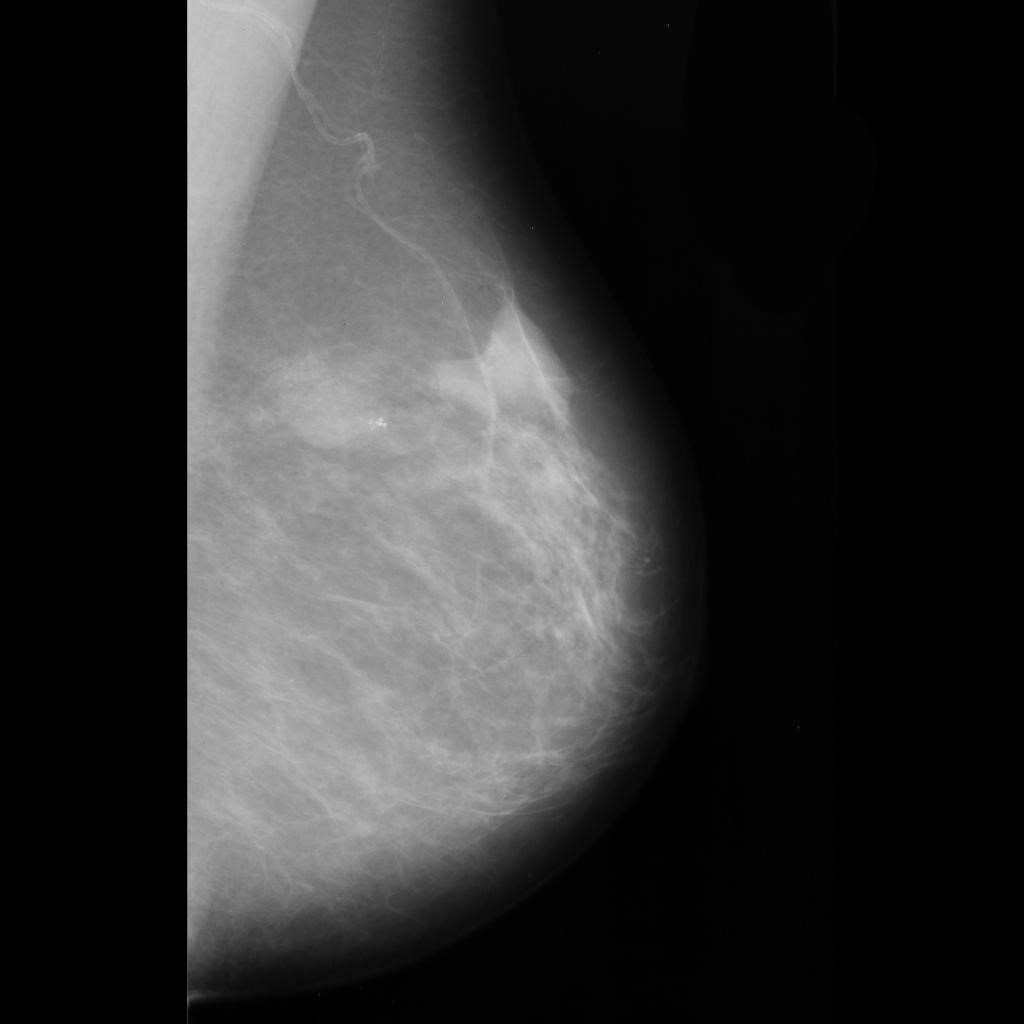

malignant